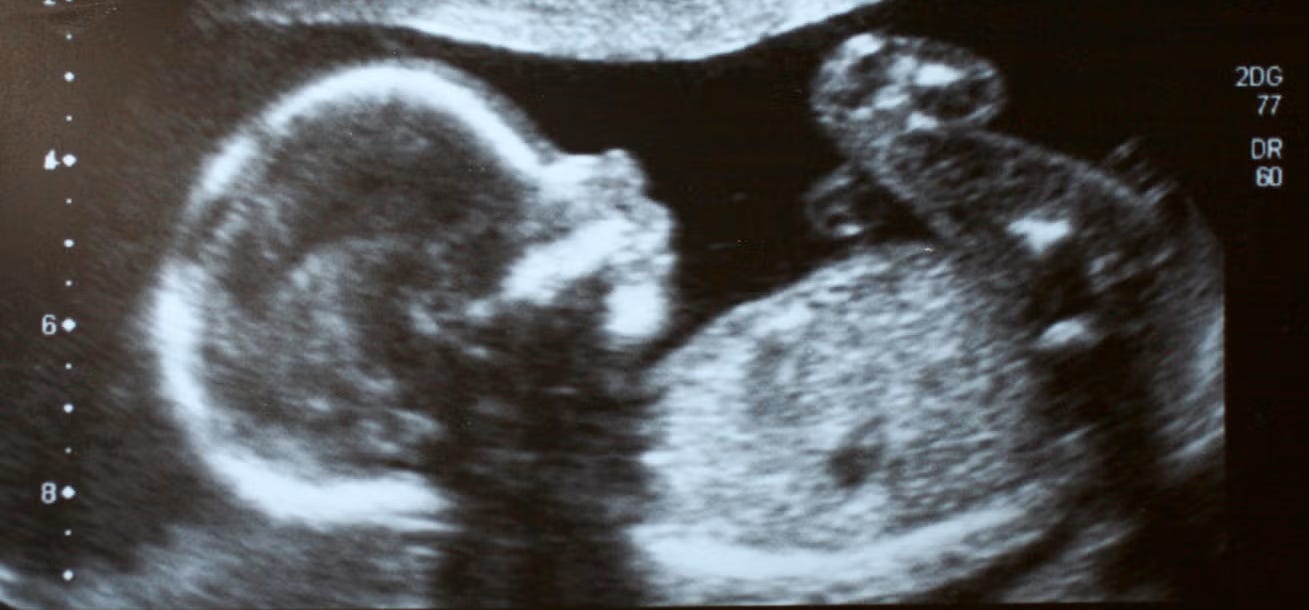

2.) “The Beginning of Life in Judaism (Article) — According to Jewish law, human life begins at birth, not conception.” Please read the article linked above, then read the blog we wrote in 2012, which has 216K likes. The like button quit working a few months ago, just so you’re aware. Our blog: “The Bible Tells Us When A Fetus Becomes A Person”Becomes A Person.” Trolls will say, “It doesn’t matter how many likes it has. It’s still lies!” No, it isn’t, but they are so tied to the views they think sets them apart, they can’t even entertain the truth in their minds.